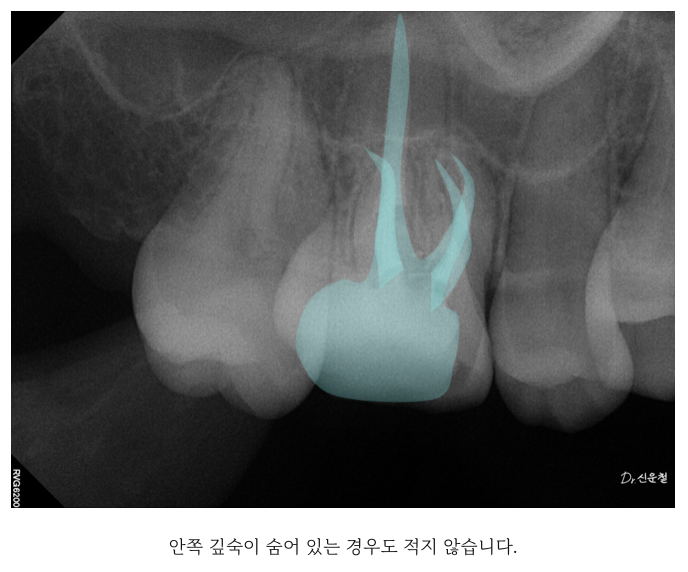

문제는 치아 안 구조가 생각보다 훨씬 복잡하다는 점입니다.

겉으로는 뿌리가 하나처럼 보여도 실제로는 여러 갈래의 신경관이

안쪽 깊숙이 숨어 있는 경우가 적지 않습니다.